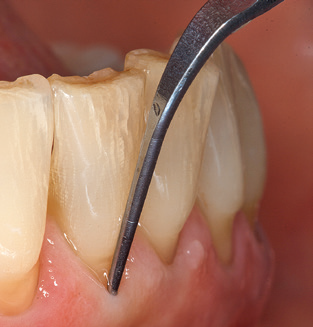

Good illumination of the working field facilitates the process considerably. The system used by the authors achieves this thanks to a 5x LED ring integrated in the handpiece. Naturally, a range of working tips for different indications is also offered. A straight, universally employable tip is the basic instrument required for machine cleaning of natural teeth (Fig. 5a and b). Curved tips, which allow access to exposed furcations, are also available for hard-to-reach areas in the posterior region (Fig. 6).

Fig. 4: Flexible probes with millimetre markings are recommended for the probing of dental implants (e.g. Colorvue Kit PCV11KIT6, Hu­Friedy). – Fig. 5a and b: A straight working tip (1P, W&H Dentalwerk Bürmoos GmbH) is a suitable instrument for use on all natural teeth. – Fig. 6: Curved working tips (3Pr/3Pl, W&H Dentalwerk Bürmoos GmbH) lend themselves to the processing of difficult-to-reach areas of the tooth and root surfaces (e.g. furcations). – Fig. 7: The tapered, hexagonal implant cleaning tip (1I, W&H Dentalwerk Bürmoos GmbH) permits atraumatic and efficient cleaning of the crown and abutment surfaces. – Fig. 8: Titanium and carbon curettes are suitable instruments for the manual cleaning of the implant surfaces.